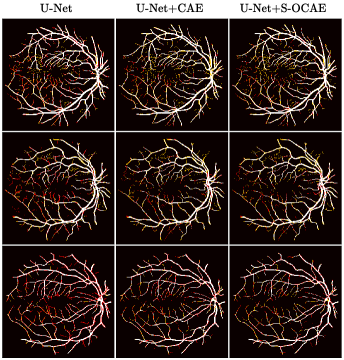

Refer to caption

Fig. 4: Retinal vessel segmentation results. True positives, false positives and false negatives are in white, red and yellow.

U-Net [4] using VGG13 with BN pre-trained on ImageNet as encoder [6] was compared with the same U-Net architecture complemented with shape priors from either a standard CAE (U-Net+CAE) [12] or the proposed S-OCAE (U-Net+S-OCAE). Both auto-encoders were trained from scratch.

Quantitative results (Tab.1) indicate that adding shape priors to U-Net significantly improves delineation results in all assessment metrics. Moreover, whatever the dataset, the proposed method outperforms U-Net+CAE in DSC, AVD, ASSD, and HD except for 3D-IRCADb where U-Net+CAE reaches a slightly better DSC. The main improvement from U-Net+CAE to U-Net+S-OCAE is observed at the level of the HD metric which undergoes a rise of 3.08%percent3.083.08\% for DRIVE and 4.03%percent4.034.03\% for 3D-IRCADb. The attenuation of the largest segmentation errors suggests that vessel contours provided by U-Net+S-OCAE are more suitable with respect to clinical requirements. Results without and with CB reveal the positive impact of making communicate under and overcomplete features. In addition, vessel delineations displayed in Fig.3 and 4 highlight a better ability of U-Net+S-OCAE to extract small structures against other methods, while providing less false positives. These results tend to indicate that relying on a semi-overcomplete embedding to produce shape priors leverages a robust representation of the vascular tree geometry, despite the large range of various multi-scale structures visible in both DRIVE and 3D-IRCADb datasets.